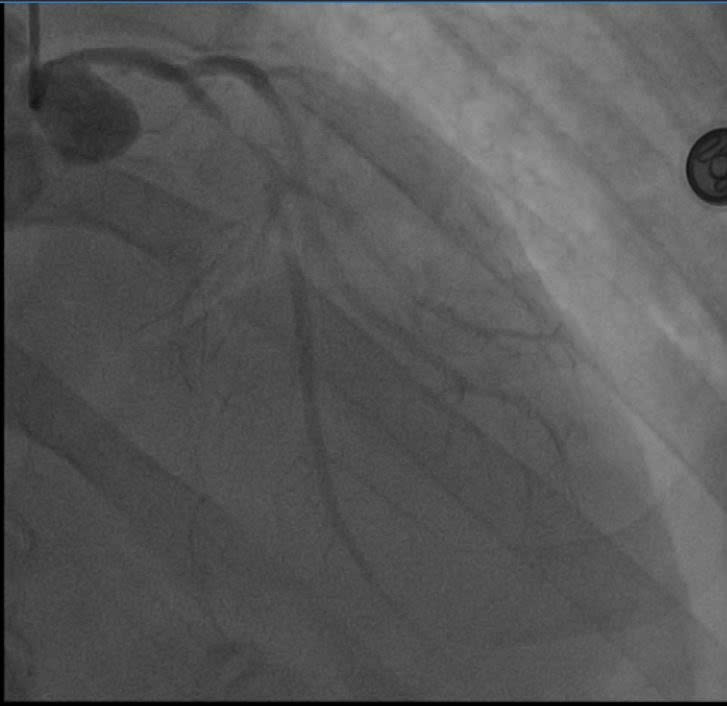

Cuộc chạy đua với thời gian: Khi y học hiện đại "hồi sinh" trái tim

Các bác sĩ Bệnh viện E vừa cấp cứu vừa hồi sức và khẩn trương thực hiện các thăm dò cận lâm sàng tìm nguyên nhân cho người bệnh. Kết quả chụp động mạch vành đã hé lộ nguyên nhân thực sự: Động mạch liên thất trước (LAD) – nhánh động mạch quan trọng nhất nuôi tim – đã bị tắc nghẽn tới 99%. Đây là hậu quả của tình trạng xơ vữa lan tỏa, dù trước đó anh M. chỉ có biểu hiện đau thắt ngực nhẹ mà anh lầm tưởng là trào ngược dạ dày.

Các bác sĩ thực hiện can thiệp mạch vành qua da (PCI) cho người bệnh. Kết quả chụp mạch số hóa xóa nền (DSA) xác định tổn thương hẹp khít 99% đoạn gần nhánh liên thất trước (LAD) – vốn được mệnh danh là "động mạch của sự sống". Các bác sĩ tim mạch can thiệp đã nhanh chóng triển khai kỹ thuật đặt Stent, giải phóng điểm tắc nghẽn, tái lập dòng chảy mạch vành để cứu vãn vùng cơ tim đang thiếu máu cục bộ cấp tính và ngăn chặn các cơn loạn nhịp nguy hiểm.